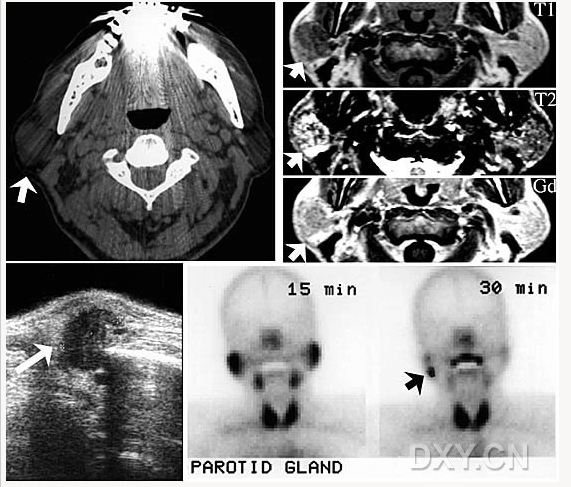

舍格倫綜合征

涎石病

腺淋巴瘤[沃辛瘤